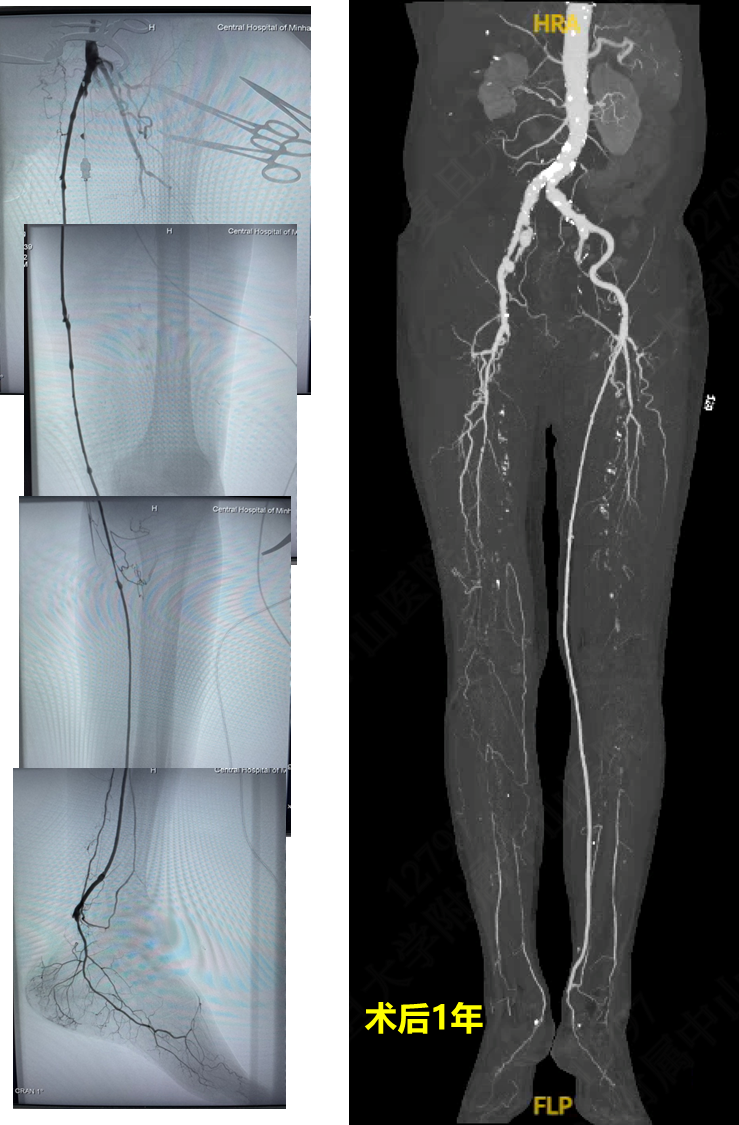

技术失败:R5 ischemia → 股总-远端胫后In-situ GSV旁路

4次EVTs反复复发:R5 ischemia → 腘P3-足背non-reversed GSV旁路

EVT后临床失败:R5 ischemia → 腘P3-足底动脉 reversed GSV旁路